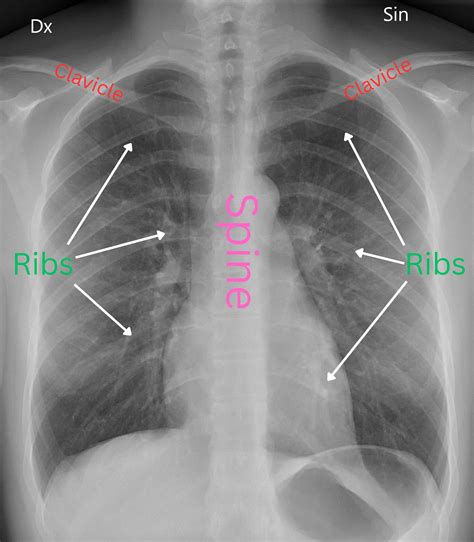

La silicosis es una enfermedad difícil de detectar por la persona expuesta, sobre todo en etapas iniciales. Por ello, es de suma importancia que su diagnóstico sea establecido por un médico especialista a través de diversos estudios, como por ejemplo una radiografía de tórax.

El diagnóstico se basa en la historia clínica de exposición laboral, síntomas respiratorios y hallazgos en estudios de imagen. Una vez hecho el diagnóstico radiológico, según la norma internacional de neumoconiosis de la OIT, la incapacidad mínima que se asigna al paciente es del 25%.